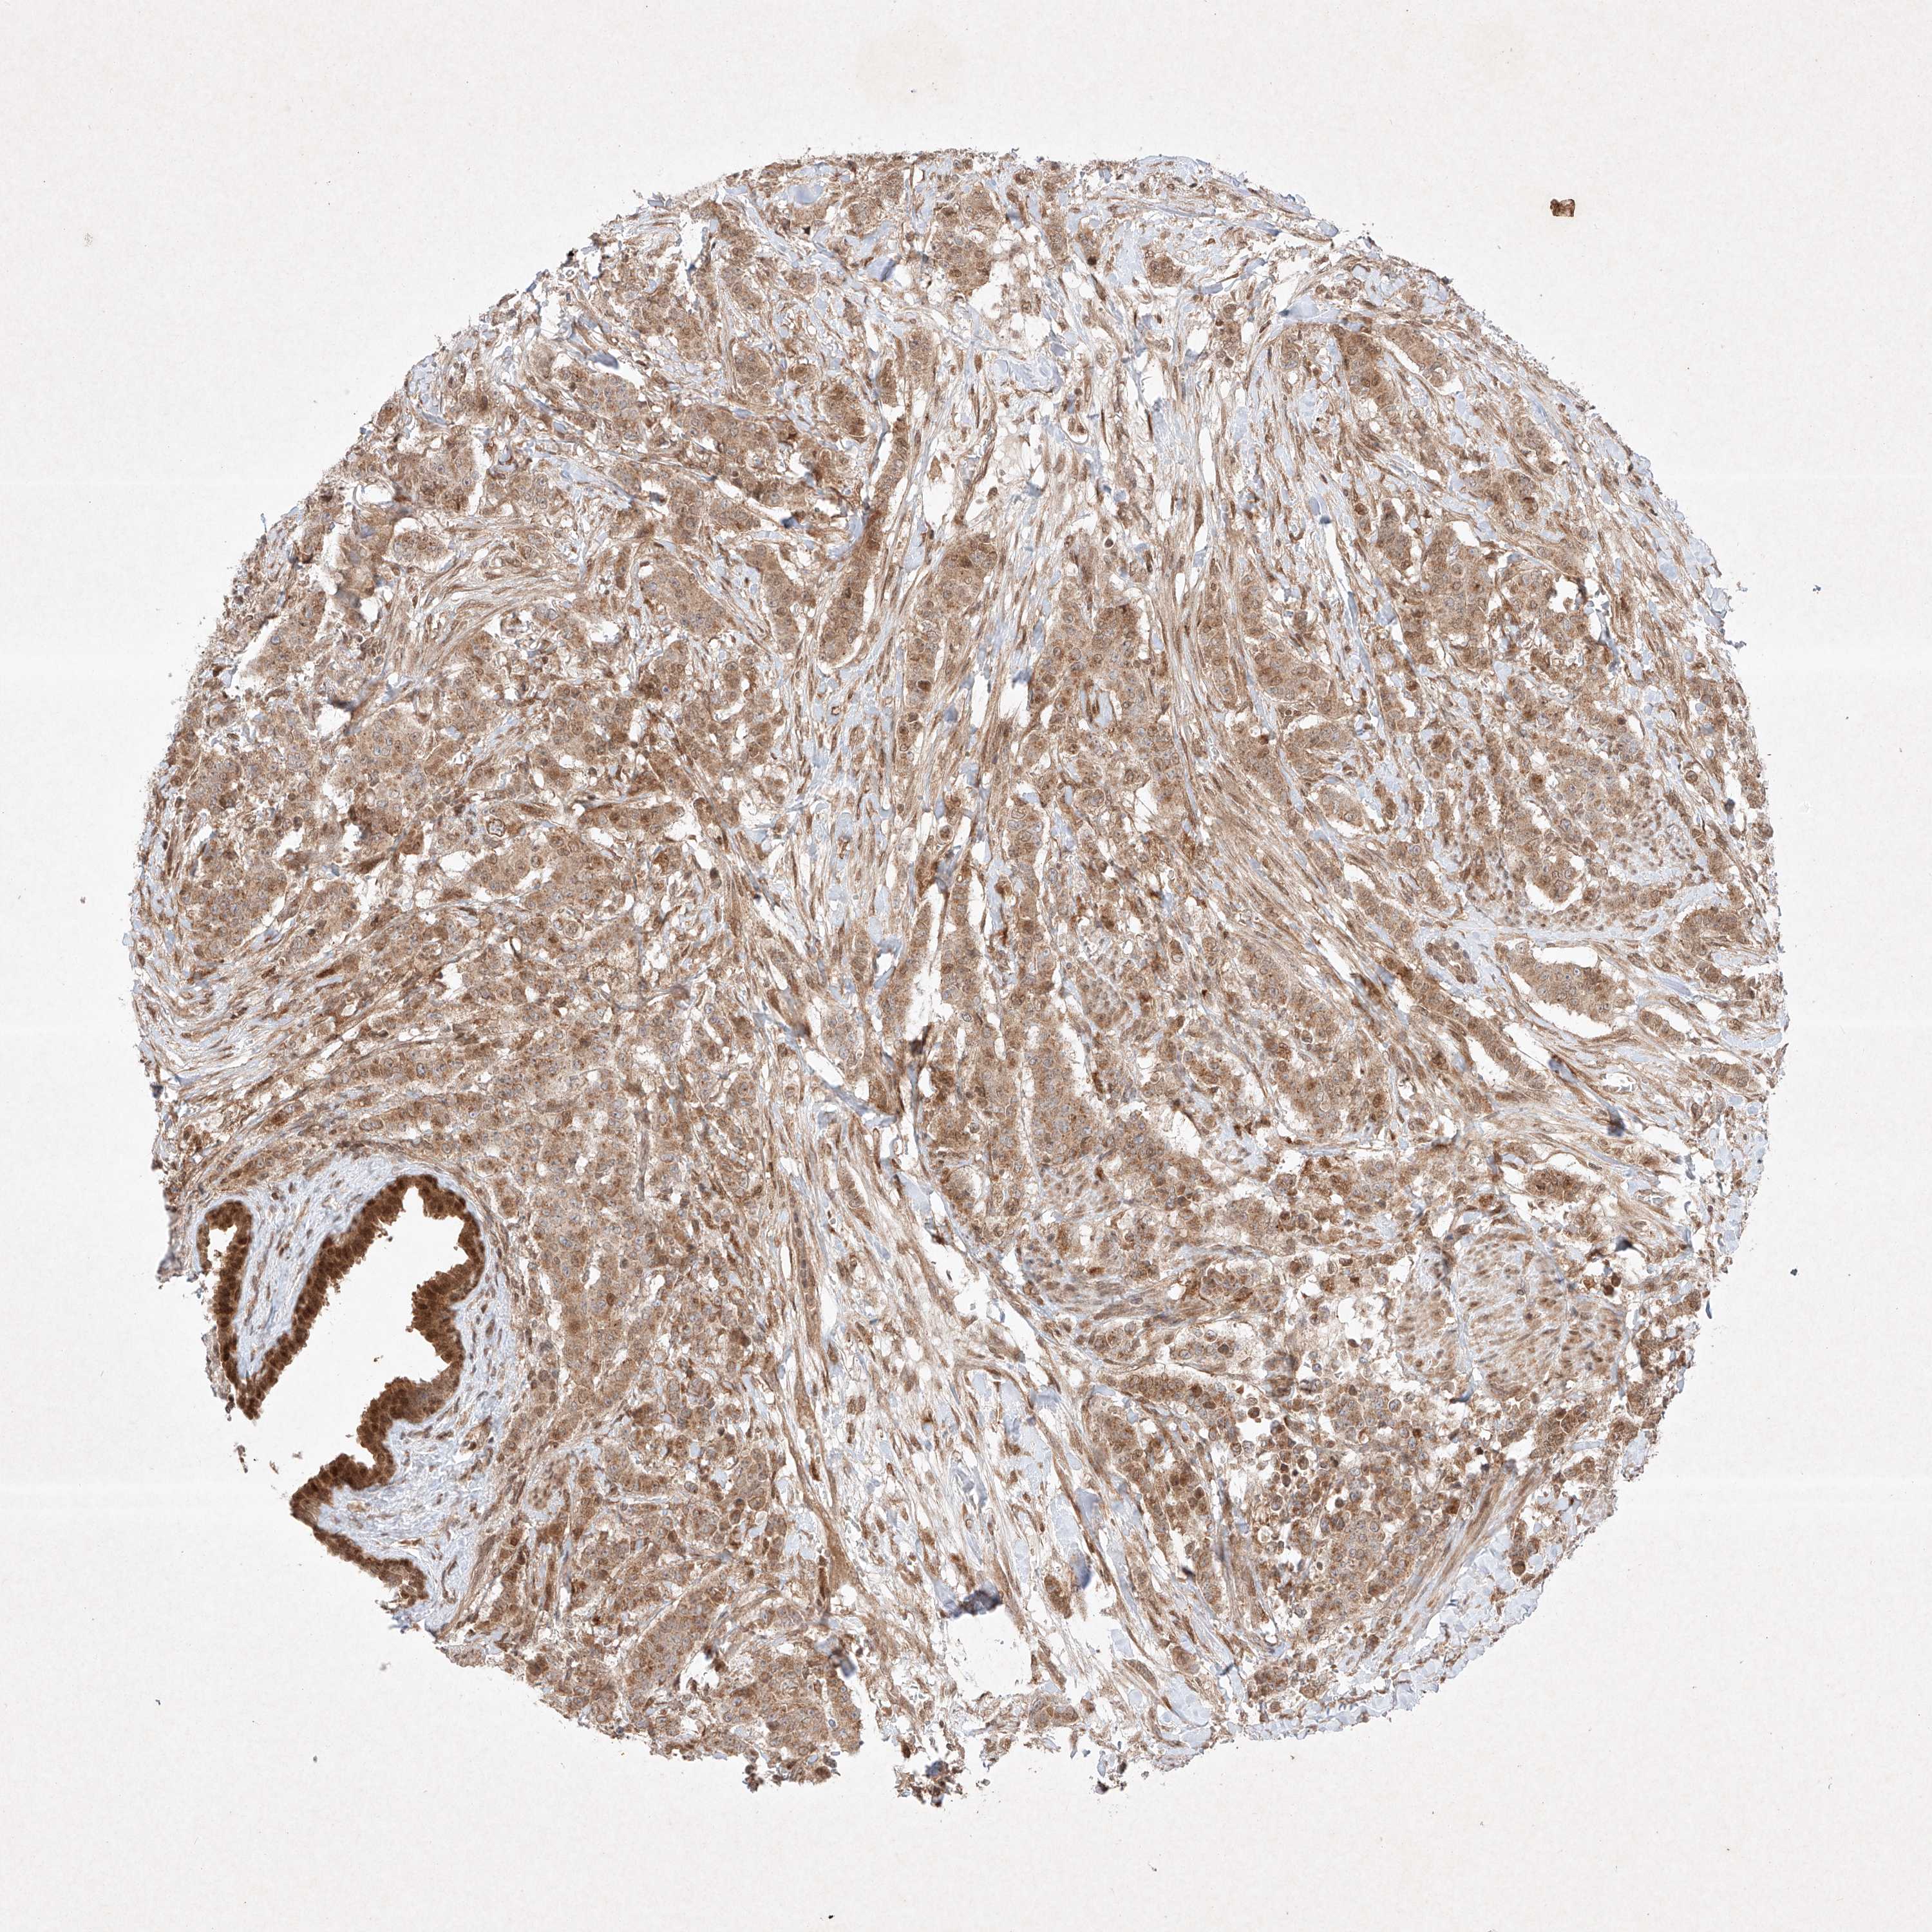

BRCA TCGA BRCA VALIDATION PROTEIN EXPRESSION